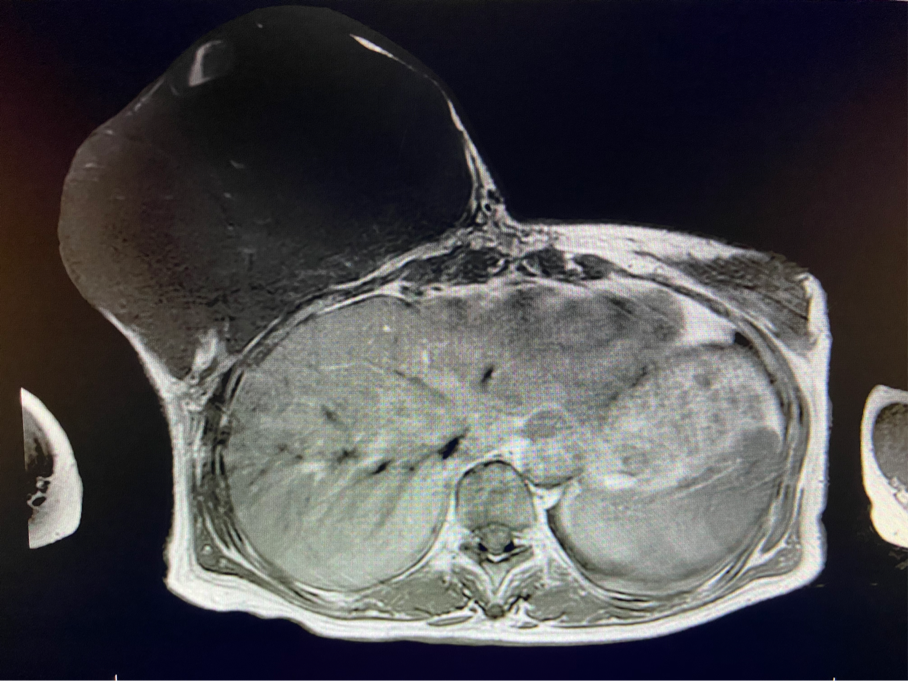

6個(gè)月前,王女士能感覺(jué)到右乳腫物明顯增大至“鴨蛋”一般,而且伴有局部皮膚瘙癢及輕度脹痛,可這次王女士并沒(méi)有那么幸運(yùn),服藥3個(gè)月不僅沒(méi)有控制住腫物,脹痛也越發(fā)嚴(yán)重,超聲檢查提示:右乳囊實(shí)性占位,最大前后徑約10.8cm,右腋窩多發(fā)腫大淋巴結(jié),遂行右乳腫物穿刺活檢術(shù),術(shù)后病理檢查提示:右乳腫物穿刺乳腺組織2條,均可見(jiàn)導(dǎo)管囊性擴(kuò)張,部分區(qū)域間質(zhì)纖維增生,其中1條內(nèi)導(dǎo)管上皮成普通型增生。輾轉(zhuǎn)當(dāng)?shù)囟嗉裔t(yī)院藥物治療后,錢(qián)沒(méi)有少花,但是療效甚微。

2周前,王女士的右乳外下方皮膚破潰,伴大量滲液,還發(fā)出陣陣惡臭。經(jīng)多方打聽(tīng),王女士從外地來(lái)到西安國(guó)際醫(yī)學(xué)中心醫(yī)院甲乳外科劉曉敏主任處就診。入院后,迅速完善了一系列相關(guān)術(shù)前檢查:王女士的雙乳外形不對(duì)稱,右乳約22?20cm,皮膚水腫明顯并可見(jiàn)靜脈曲張。右乳外下象限皮膚可見(jiàn)局部破潰,創(chuàng)面有3處,共約6?4cm大小,創(chuàng)面呈暗紅色,伴有血性滲出及惡臭,局部皮膚溫度升高。右側(cè)腋窩可觸及腫大淋巴結(jié)。

該患者右乳巨大腫物術(shù)前初步考慮乳腺葉狀腫瘤可能,因腫瘤太大,幾乎遍及整個(gè)右側(cè)乳房,為保證“無(wú)瘤原則”,術(shù)中切除范圍位置未知,極有可能出現(xiàn)皮瓣缺損。于是,經(jīng)過(guò)和整形醫(yī)院郭樹(shù)忠院長(zhǎng)、整形外科王愛(ài)武主任的討論,提供了兩種手術(shù)方式,一是創(chuàng)面修復(fù)(植皮或轉(zhuǎn)移皮瓣修復(fù)創(chuàng)面),二是乳房再造,與患者及家屬溝通后,決定先解決腫物,3年病情不再?gòu)?fù)發(fā)后,可以再考慮乳房重建。